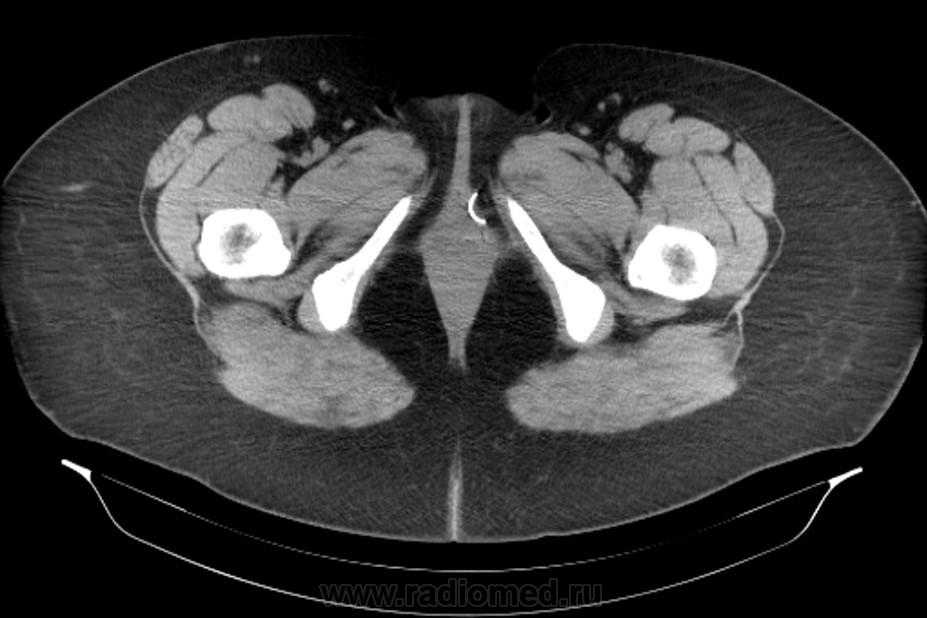

Инородное тело. Хирургическая игла.

Хирургическая игла, которую оставили гинекологи.

Да, гинекологи сами почуяли неладное и отправили пациентку на исследование. Операция была по поводу кисты левой бартолиневой железы. Со слов пациентки, ей до этого делали УЗИ, но ничего не обнаружили. Расположена она в толще большой половой губы, в преддверии влагалища.